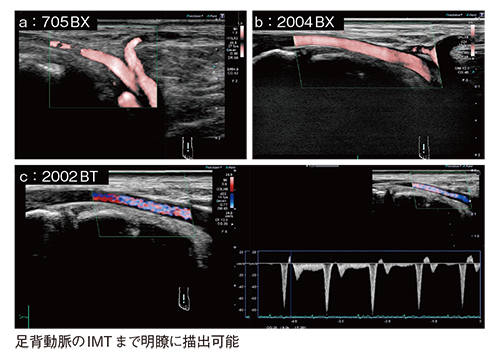

図10は,プローブによる足背動脈の描出能の違いであるが,従来型リニアプローブ(a)と比較し,24MHzリニアプローブ(b)ではより表在に近い血管まで明瞭に描出され,22MHzホッケー型リニアプローブ(c)でも描出能は同等であり,血流の評価も可能である。

図10 プローブによる足背動脈の描出能の違い

22MHzホッケー型リニアプローブで特筆すべきは,例えば,前脛骨動脈や足背動脈においてもIMTを明瞭に描出可能なほか,プローブの形状を生かして圧迫法を用いることも可能なことである(図11)。画質はPLI-705BXと遜色なく,IMTの描出においては,むしろ22MHzホッケー型リニアプローブの方が良好である。

図11 22MHzホッケー型リニアプローブによる前脛骨動脈および足背動脈のIMTの描出